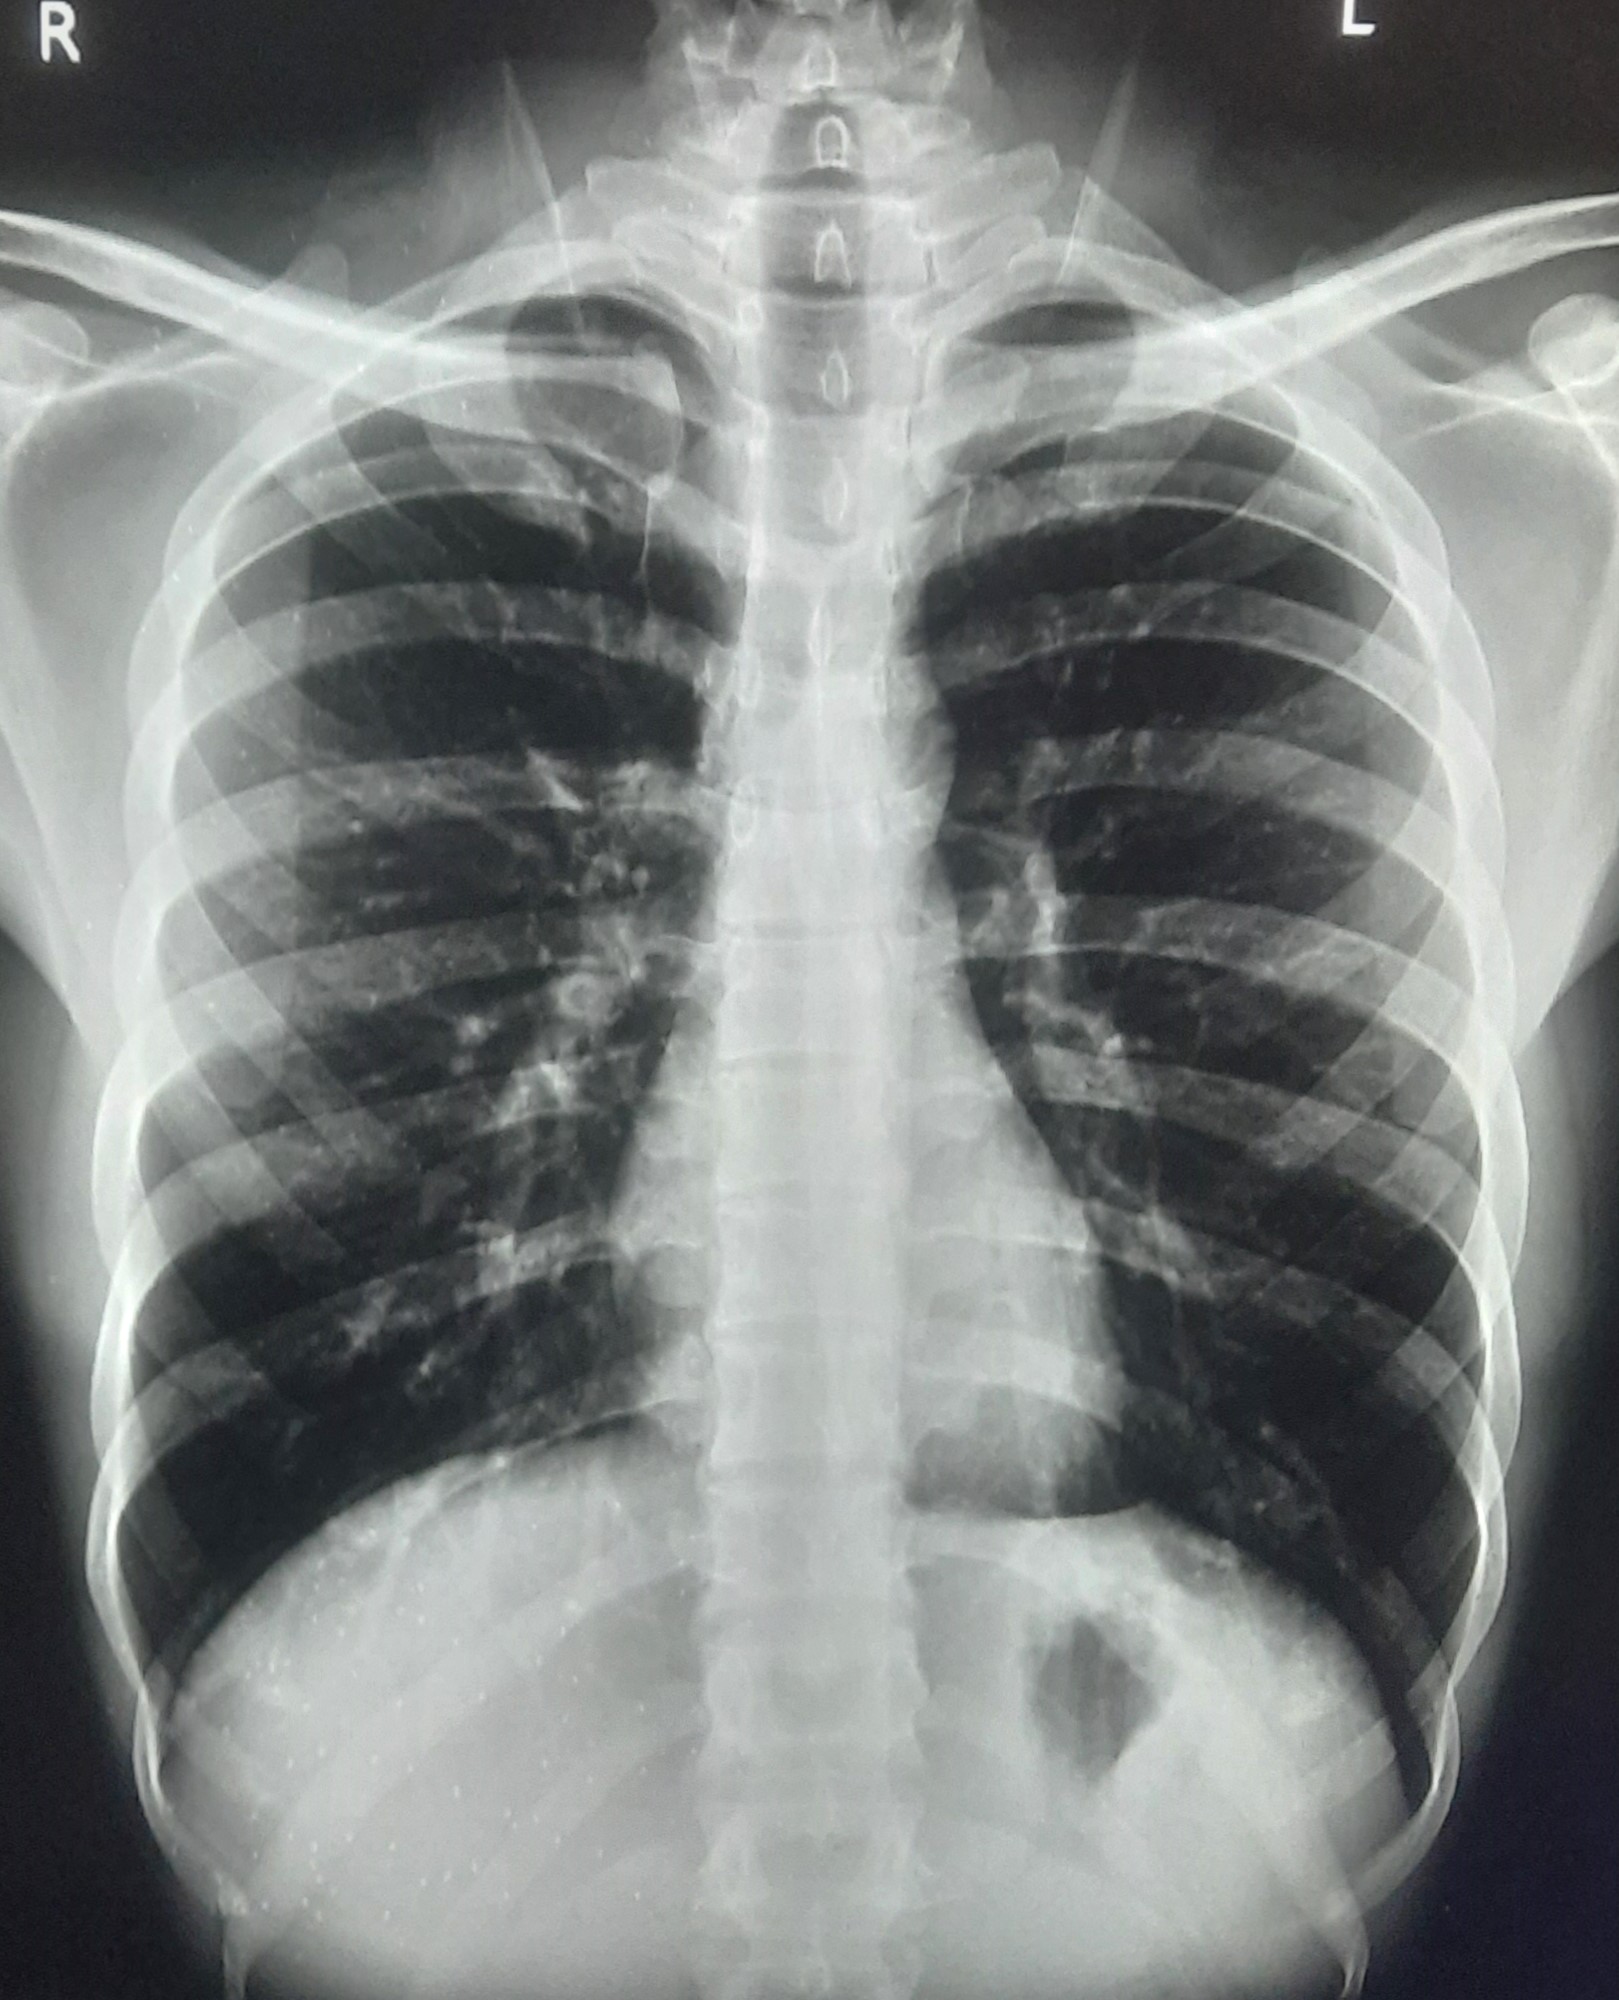

| 297 | IGGMC, Nagpur, Nagpur | P2 | 29-4175 | Sabina Parveen | Consent taken on Paper | 23 Yrs. |

Provisional Diag : PTB Reactivation

Final Diag : ? |

TB Case (Confirmed) | Bilateral Middle Lower Zone Pulmonary TB | Abnormality visible on x-ray |